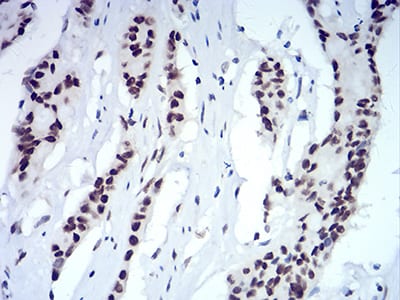

Immunohistochemical analysis of paraffin-embedded human colon cancer tissues using CBX5 mouse mAb with DAB staining.

Immunohistochemical analysis of paraffin-embedded human colon tissues using CBX5 mouse mAb with DAB staining.